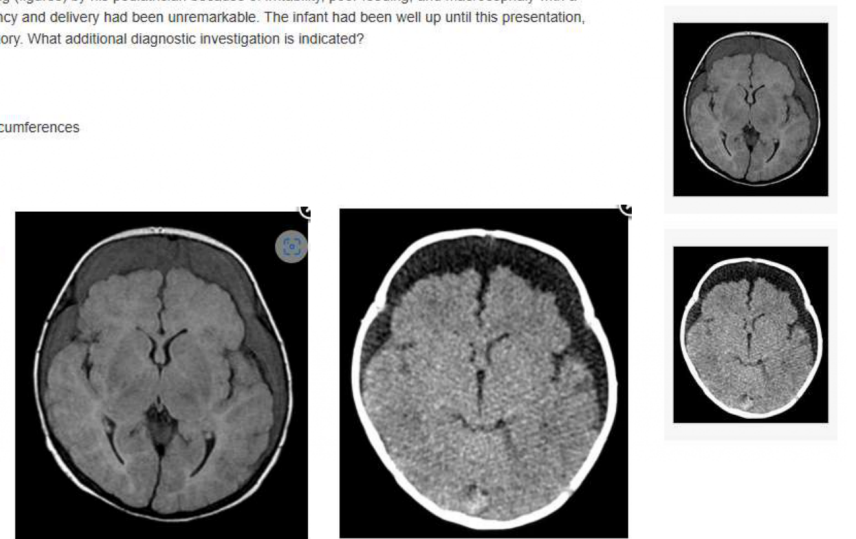

A 6-month-old infant presents with enlarging head circumference, full anterior fontanelle, splitting of the cranial sutures and developmental delay. The results of a neurological examination are otherwise normal. Computed tomographic scans are obtained

(Figures 1 and 2). What is the most likely diagnosis?

A

Dandy-Walker malformation